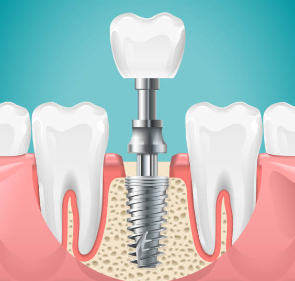

임플란트의 사전적 의미는 다음과 같습니다. 임플란트는 상실된 치아를 인공 치아 이식을 통하여 건강한 구강을 가지게 하는 의학 분야를 뜻합니다.

본래에는 인체의 조직이 상실되었을 때 이를 회복시켜 주는 대체 물질을 의미하지만, 치과에서는 인공 치아 이식의 의미를 지니기도 합니다. 이해를 쉽게 하기 위하여 다시금 말씀드리면, 인공적인 치아를 상실된 치아부위의 잇몸 뼈에 식립을 한 후, 그 위에 인공치아를 장착하여 수복하는 치료 방법을 말하는 것입니다.

2. 치아 발치 및 1차 시술

임플란트가 필요한 치아의 발치를 실시한 후, 그곳에 1차 시술을 진행합니다. 1차 시술은 턱뼈에 임플란트 인공치근을 식립하고 잇몸을 덮는 과정을 뜻하며, 이 과정에는 필수 기간이 필요하며 일정기간 동안 인공치근과 턱뼈가 잘 붙도록 기다려야 하는데, 일반적으로 아래턱은 약 2~3개월, 윗턱은 약 4~6개월 소요됩니다.

3. 2차 시술

인공치근이 잇몸뼈에 잘 자리 잡은 후, 덮어진 잇몸을 다시 열어 인공치근을 밖으로 노출시킵니다. 이때 진행하는 시술을 인공치근과 지대주를 연결하는 2차 시술이라 합니다. 지대주는 인공치근과 치아머리 크라운을 연결하는 기둥 역할을 하며, 2차 시술 후 잇몸이 완치되는데 약 1~2주 정도 걸립니다.